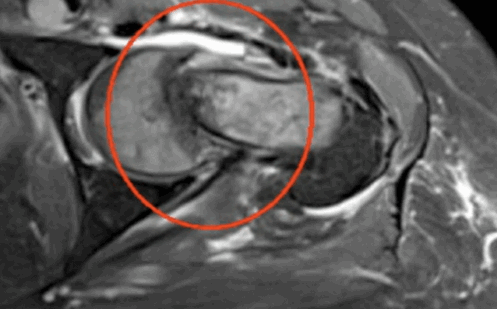

Импиджмент синдром на МР-фото

К механическому конфликту между бедренной головкой/шейкой и краем вертлужной впадины приводят одно- или двусторонние дефекты костей врожденного или приобретенного генеза. Видоизмененные компоненты сочленения вызывают дисфункцию конечности за счет соударения во время движения. Патологическое трение костей способствует разрастанию остеофитов на фоне постоянной травматизации вертлужной губы. Если своевременно не диагностировать заболевание и не начать лечение, последняя с течением времени разорвется., Хрящевая ткань сочленяющих костей будет разрушена. Подобный механический конфликт часто способствует формированию коксартроза и сопровождается прогрессирующим болевым синдромом.

МРТ: метастаз в шейку бедра с формированием стресс-перелома (обведено)